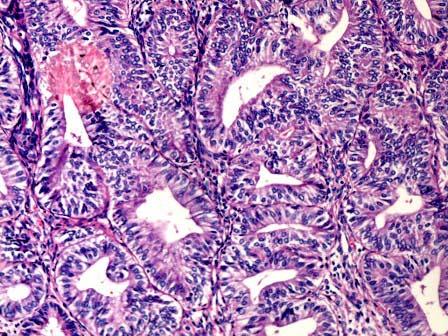

问题 女性,46岁,阴道不规则出血1年,诊刮子宫内膜,显微镜下见腺体增生密集,与间质比>3:1,腺体呈乳头状,可见背靠背现象,伴嗜酸性粒细胞浸润,腺上皮异型性并见核仁(如图),应诊断为 ( )

选项 A.子宫内膜单纯性增生 B.子宫内膜复杂性增生 C.子宫内膜单纯性增生伴非典型增生 D.子宫内膜复杂性增生伴非典型增生 E.子宫内膜腺癌

答案 D